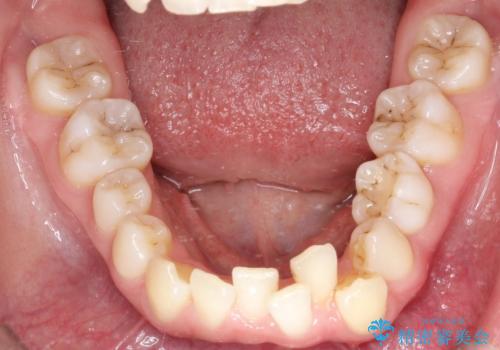

前歯のガタガタと欠損部を改善

- 患者様は、前歯のガタガタ(叢生)と左下5番の欠損部が気になるとのことで来院されました。診断の結果、インビザラインを用いて前歯の叢生を整えながら、左下5番の欠損部にはインプラント治療を計画しました。矯正治療により、歯並びを改善すると同時に、噛み合わせのバランスも向上させることを目標としました。矯正期間とインプラントの治療計画を並行して進めることで、患者様のご希望に応えるプランを立てました。

前歯の叢生改善のため、インビザラインによる透明で目立たない矯正装置を使用しました。治療中は、歯の移動による負担を最小限に抑えつつ、歯列全体のバランスを考慮して進めました。左下5番の欠損部には、矯正終了後にインプラントを埋入し、自然で機能的な咬合を回復しました。治療期間中、患者様には装置の正しい装着と日々の清掃を徹底していただき、歯肉やインプラント周囲の健康を保つようサポートしました。結果として、美しい歯並びと快適な噛み合わせを両立させることができました。